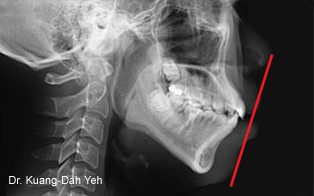

矯正前